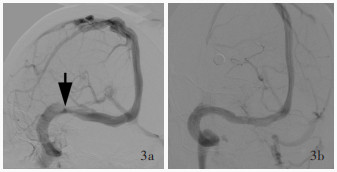

Higgins JN , Owler BK , Cousins C , Pickard JD . Venous sinus stenting for refractory benign intracranial hypertension. Lancet, 2002, 359: 228- 230.

Elder BD , Goodwin CR , Kosztowski TA , Radvany MG , Gailloud P , Moghekar A , Subramanian PS , Miller NR , Rigamonti D . Venous sinus stenting is a valuable treatment for fulminant idiopathic intracranial hypertension. J Clin Neurosci, 2015, 22: 685- 689.

Li BM , Liang YP , Cao XY , Wang J , Liu XF , Yang CS , Wang CM . Image anatomic characteristics and clinical diagnosis and treatment of cerebral venous sinus stenosis. Zhonghua Yi Xue Za Zhi, 2015, 95: 3505- 3508.

李宝民, 梁永平, 曹向宇, 王君, 刘新峰, 杨春水, 王传明. 脑静脉窦狭窄的影像解剖特征与临床诊治的探讨. 中华医学杂志, 2015, 95: 3505- 3508.